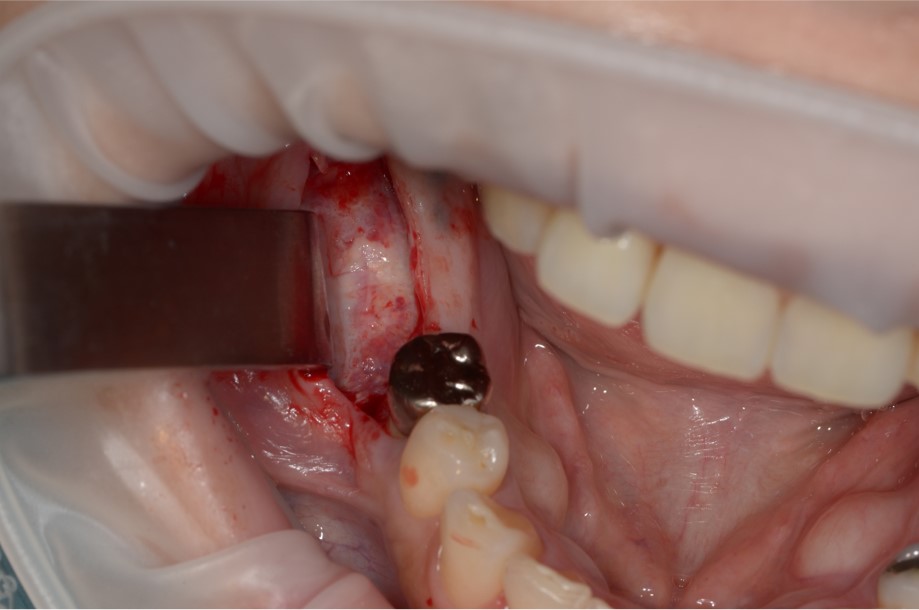

人工骨を充填するだけでは骨を十分に作れない時、患者さんが人工骨の使用に抵抗がある時に、口の中の骨を移植します。